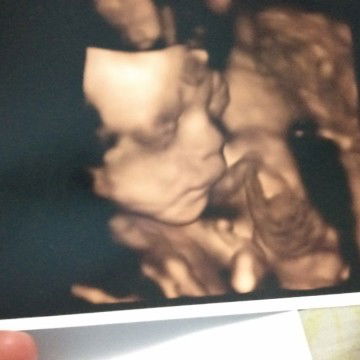

Menunggu debay launching

hai.. bunda, ini aku waktu umur 28week.. dan sekarang aku sudah berumur 37week.. bundaku lagi harap2 cemas nunggu launchingnya aku nih bunda2 cantik.. doakan kami selalu sehat ya, semoga nnt aku bisa bertemu dengan bunda dengan mudah, sehat, dan lancar yaa.. mudah2an bunda yg lain jg diberi kelancaran menjalani kehamilan dan persalinan nnt.. ?? semangat bunda2 semua..